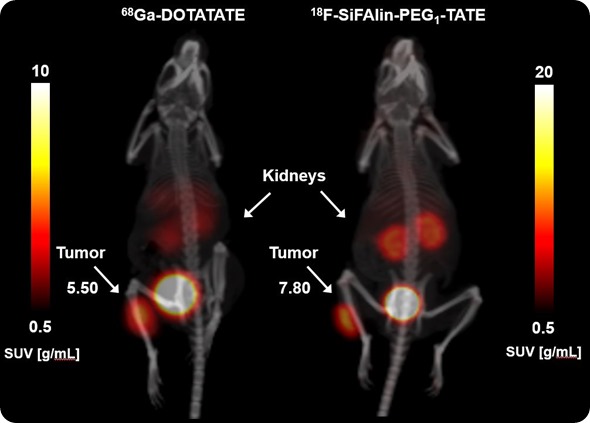

Another one is the detection of cancer in a gastric cancer model, together with the second medical department here at the University Hospital. Our own research was designing the molecules by multimerization of target structures and then the tests in a mouse tumor model.

In the in vivo Xtreme and the Bruker Albira PET/SPECT/CT, it's the pharmacokinetics of our new radiotracers or for our new fluorescent dyes coupled to target structures.